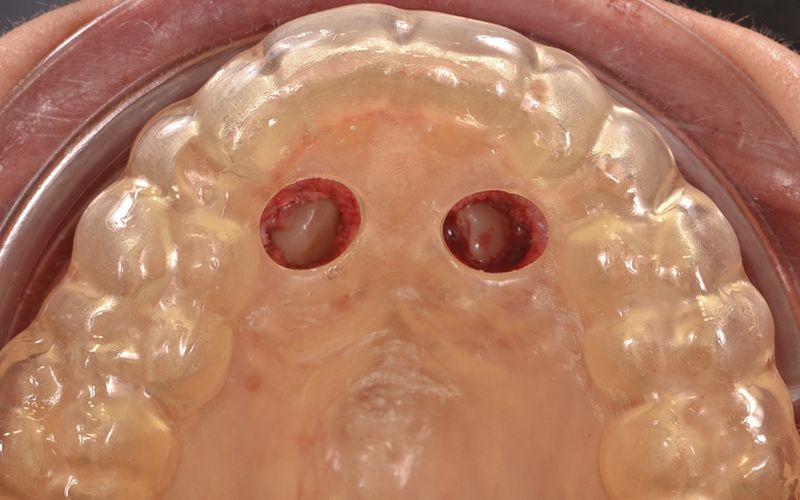

Fruto del trabajo en I+D+I, y de la capacidad productiva en el ámbito de la impresión 3D y de los materiales, en Avinent lanzamos alineadores invisibles personalizados para resolver todos los retos estéticos y funcionales. Recode Aligners, es la marca de alineadores de Avinent, que además de tratar multitud de casos con éxito, ofrece todos los recursos de comunicación para que la clínica pueda llegar a los pacientes. De igual manera, nuestra línea también incorpora otras soluciones ortodónticas como los retenedores y las férulas de descarga.